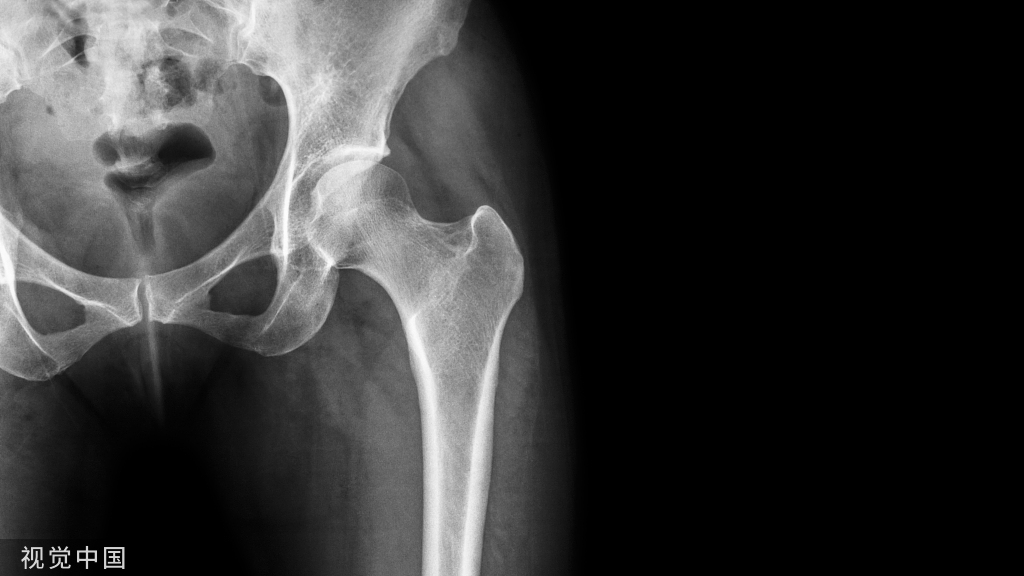

早诊断、早保头、早预防

——努力不换关节!

自己的股骨头才可能更长久!